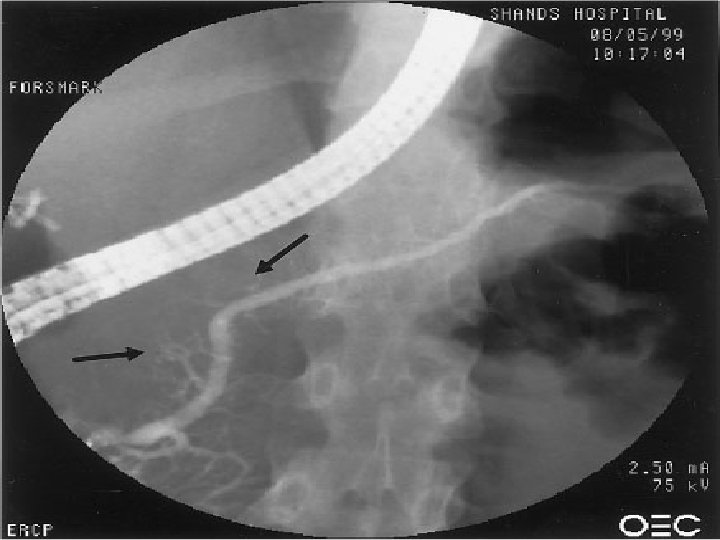

Kronik pankreatit ve endoskopik stent yerleştirilmesi